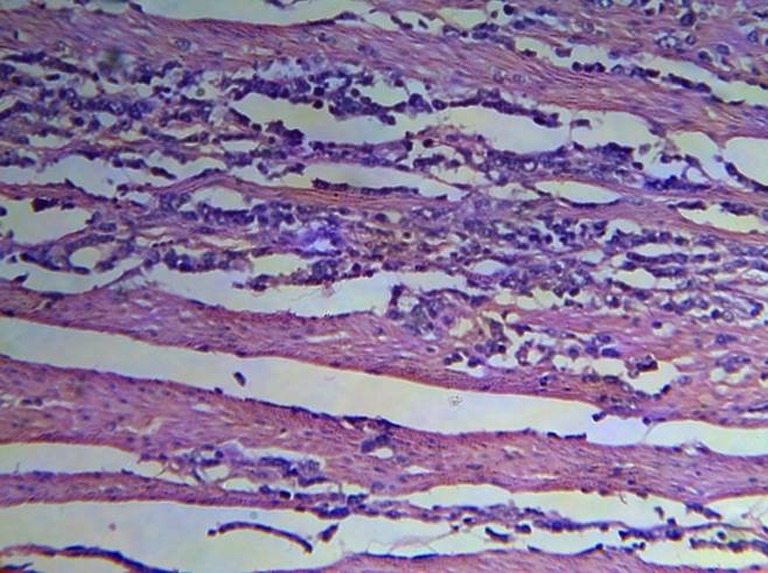

Fig. 8.

Atypical lymphoid cell infiltration in muscle bundle (H&E stain 20×)